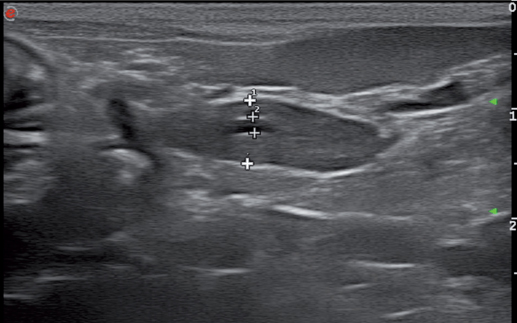

胰腺右支可见的管状结构是胰十二指肠静脉。胰腺左支的管状结构是胰管(图6)。如果不确定,是胰管还是十二指肠静脉,可以使用彩色多普勒去做区分。胰十二指肠有血流信号,而胰管没有血流信号。

20%的猫会有副胰管直接汇入十二指肠小乳头。胰管位于胰腺实质的中央,宽度为0.5-2.5mm,管壁呈高回声,管腔呈低回声。有研究表明胰管的宽度会随着年龄的增长而增加(图8.表1)。